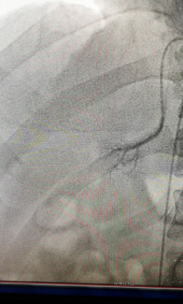

在征得患者及其家属的同意后,我院多科协作行双侧肾上腺静脉插管采血术。术中,仅仅在大腿根部局部皮肤麻醉,只需米粒大小一个针眼,通过股静脉将导管通过很多道弯曲,分别送达左侧和右侧肾上腺静脉。通过术中送检血皮质醇,证实双侧肾上腺静脉插管成功。然后,手术医生在双侧肾上腺静脉和下腔静脉同时取血。标本送检后,明确诊断为特发性醛固酮增多症,左侧肾上腺腺瘤无功能。患者无需手术,但需服用特殊的药物控制血压。在明确诊断后,心内科立即为患者调整了降压方案,针对特发性醛固酮增多症进行了针对性病因治疗。患者既往一直不能控制的血压迅速得到了良好控制。

左侧肾上腺静脉插管